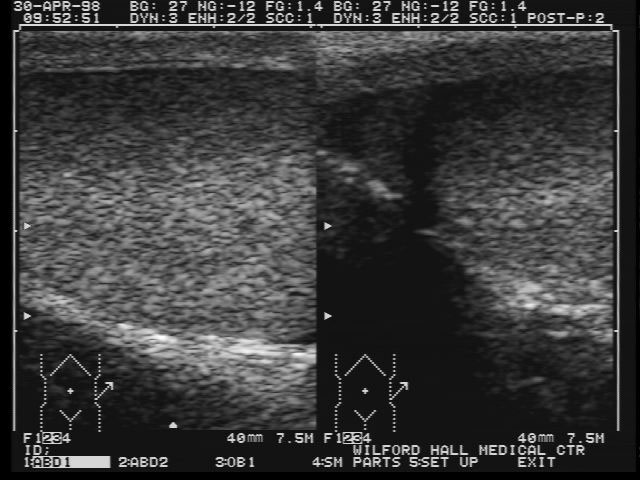

30 Apr 1998

Normal testicular ultrasound in this 23 year old Rapa Nui male with chronic testicular pain for 1.5 years. Following the normal ultrasound, a more thorough history was taken and it was found that the patient had symptoms of a urethritis for which he was subsequently treated.